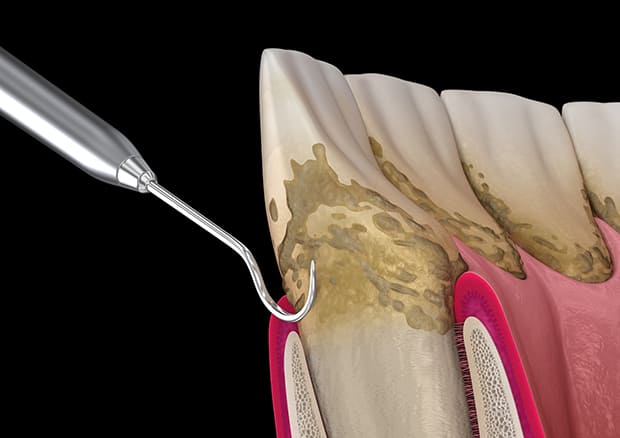

歯周病は基本治療のSRPが大切

SRPとは、スケーリング+ルートプレーニングのことです。

このSRPは歯周病治療の1つで、専用の器具や、超音波の器具を用いて歯周ポケットの中、いわゆる歯茎の中の歯の根に隠れている部分の歯垢や歯石を取り除くことです。この歯石を歯肉の縁の下につく歯石ということから、縁下歯石(えんかしせき)といいます。

縁下歯石は、図のように黒っぽい色でセメント質と同一化し強固に付着しています。

当院のSRPは、特殊な医療機器を導入することで、迅速かつ合理的に縁下歯石を除去し、歯根表面を滑沢に仕上げることによって患者様の負担を減らし、治癒効果、歯周病再発予防効果に努めています。